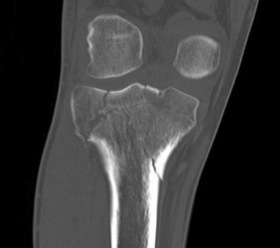

CT scan

Assess joint line

- predetermine fracture pattern before fixation

- will pick up medial condyle / bicondyle / metaphyseal fractures not seen on xray